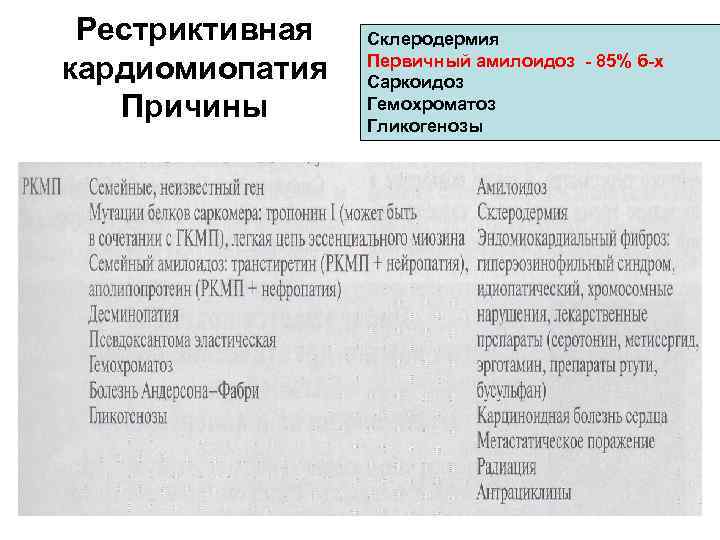

Рестриктивная кардиомиопатия Причины Склеродермия Первичный амилоидоз - 85% б-х Саркоидоз Гемохроматоз Гликогенозы

Рестриктивная кардиомиопатия Причины Склеродермия Первичный амилоидоз - 85% б-х Саркоидоз Гемохроматоз Гликогенозы